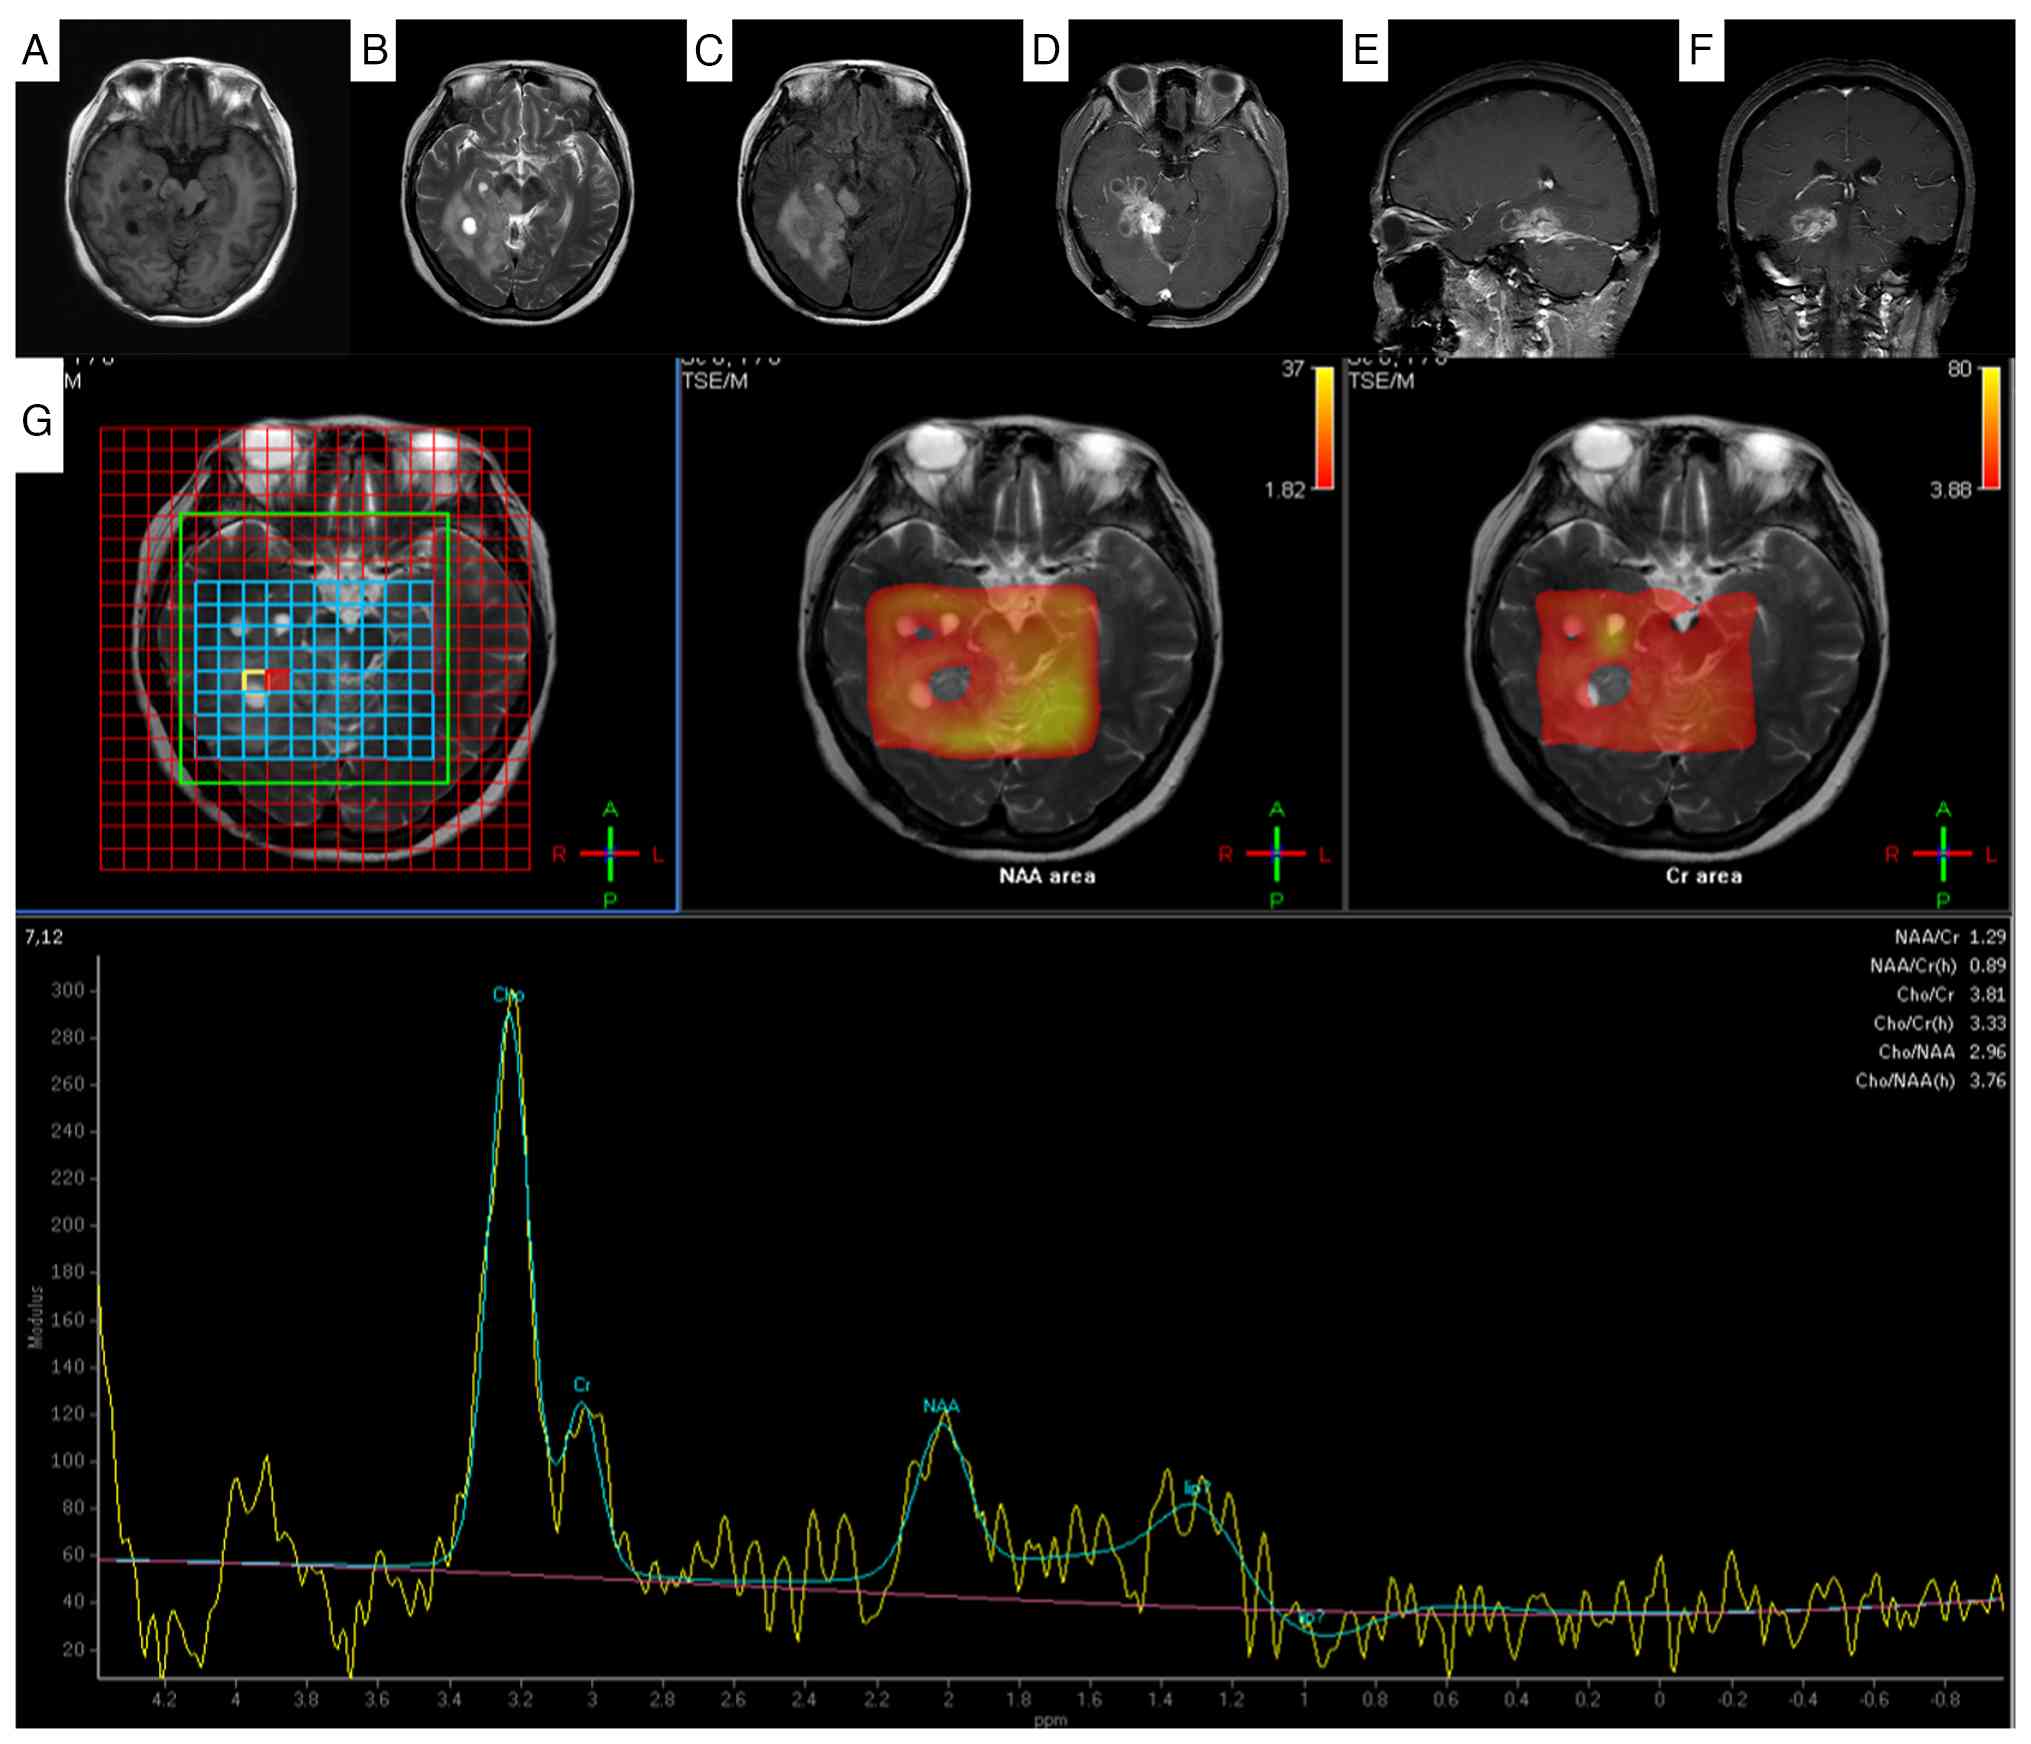

By the 12-month follow-up, the recurrent tumor had enlarged considerably, with further involvement of the right temporal lobe. The imaging revealed extensive perilesional edema, a significant mass effect with midline shift and evidence of brain herniation (Fig. 3).

Enlargement of the recurrent

gliosarcoma with brain herniation formation on 1-year follow-up

magnetic resonance imaging. The dura mater in the right occipital

region was thickened with obvious enhancement. The right cerebellar

hemisphere, right parahippocampal region and right temporal lobe

exhibited patchy mixed signal shadows. (A) On the T1WI sequence,

slightly longer T1 signals were observed, and (B) on the T2WI

sequence, slightly longer T2 signals were observed. (C)

Fluid-attenuated inversion recovery imaging shows isointense and

slightly hyperintense signals. After enhancement, the (D) axial,

(E) sagittal and (F) coronal images of the lesion exhibited obvious

inhomogeneous enhancement and annular enhancement. The lesion grows

across the tentorium, with thickening and significant enhancement

of the adjacent right cerebellar tentorium; it involves the right

portion of the brainstem, causing compression of the adjacent

fourth ventricle, right lateral ventricle and brainstem, with

leftward shift of the midline structures. (G) Magnetic resonance

spectroscopy reveals a decreased NAA peak and an increased Cho peak

in the lesion area. NAA, N-acetylaspartate; Cr, creatine; TSE/M,

turbo spin echo/magnetization.

Figure 3.

Enlargement of the recurrent gliosarcoma with brain herniation formation on 1-year follow-up magnetic resonance imaging. The dura mater in the right occipital region was thickened with obvious enhancement. The right cerebellar hemisphere, right parahippocampal region and right temporal lobe exhibited patchy mixed signal shadows. (A) On the T1WI sequence, slightly longer T1 signals were observed, and (B) on the T2WI sequence, slightly longer T2 signals were observed. (C) Fluid-attenuated inversion recovery imaging shows isointense and slightly hyperintense signals. After enhancement, the (D) axial, (E) sagittal and (F) coronal images of the lesion exhibited obvious inhomogeneous enhancement and annular enhancement. The lesion grows across the tentorium, with thickening and significant enhancement of the adjacent right cerebellar tentorium; it involves the right portion of the brainstem, causing compression of the adjacent fourth ventricle, right lateral ventricle and brainstem, with leftward shift of the midline structures. (G) Magnetic resonance spectroscopy reveals a decreased NAA peak and an increased Cho peak in the lesion area. NAA, N-acetylaspartate; Cr, creatine; TSE/M, turbo spin echo/magnetization.